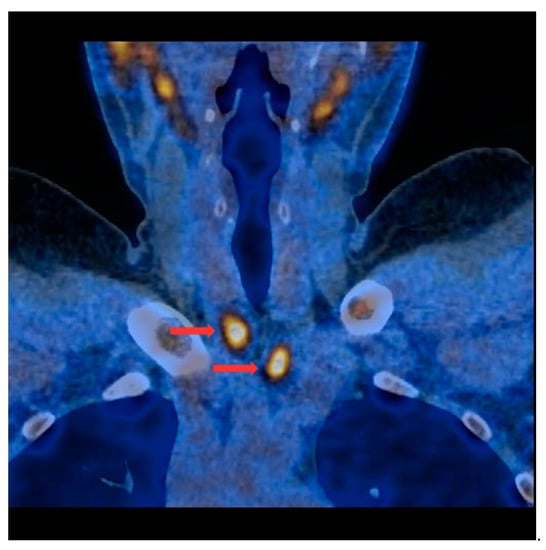

Figure 3.

PET/CT with [11C]MET—frontal projection. Two visible foci of increased radiotracer accumulation (red arrows) corresponding to the parathyroid glands (multiple lesions) below both thyroid lobes.